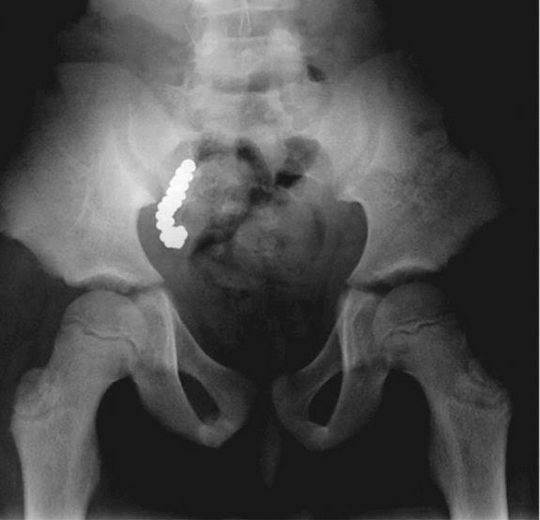

8-year old kid took the expression 'bite the bullet' personally. After doctors found out that he had high levels of lead in his blood for the last two years, and after the kid had been complaining about severe stomachache, the doctors discovered lead formations in the X-ray. Turns out, he was from a hunting family who used to gather food using lead pellets. The kid had ingested 57 pellets during a game with his siblings. All of them were found when the doctors removed his appendix.